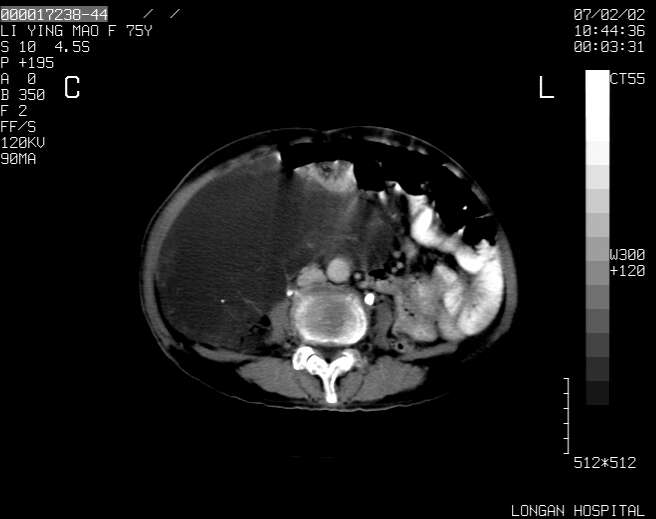

以下是引用dyqct在2007-2-10 8:53:00的发言:[br]考虑:1、肝脏多发囊肿[br] 2、左肾囊肿,右肾多发结石并积水。[br] 3、右胸少量积液。[br] 4、右肾周包裹性积液或淋巴管瘤(有见缝就钻的征象、薄隔、小结节状钙化)?[br] 5、腰椎动脉瘤样骨囊肿?[br] [br] [br]